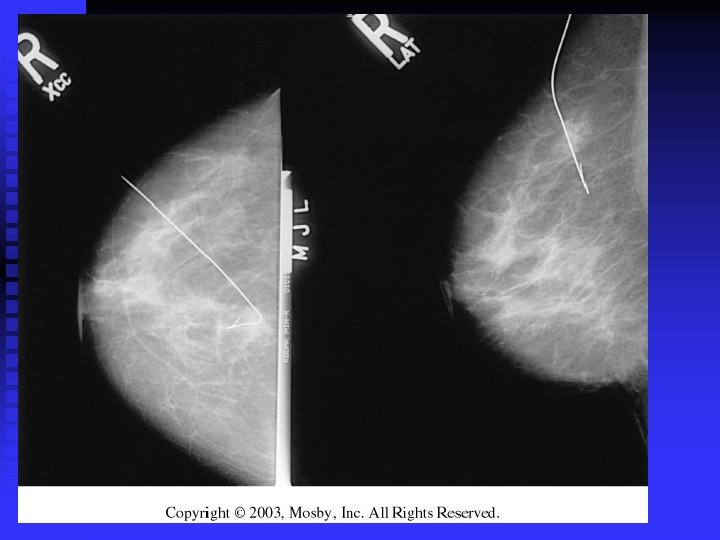

Left breast (L) contains an irregular carcinoma that is producing considerable spiculation, nipple retraction

Left breast (L) contains an irregular carcinoma that is producing considerable spiculation, nipple retraction (arrow), and skin thickening. Right breast (R) contains fibroadenoma.